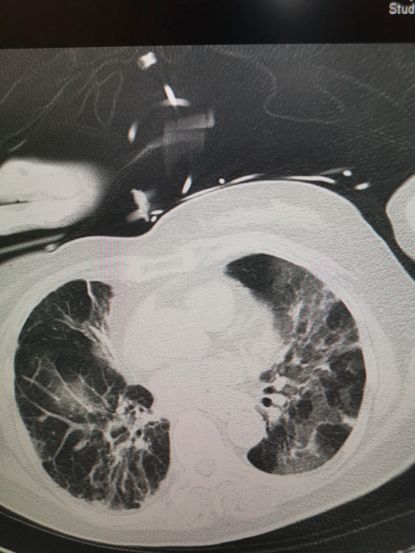

咳不出来,再加上对抗病毒的部队——淋巴细胞又减少,这两种关键的防御能力下降了。病毒不断地复制并且侵犯细胞,严重的病例,在两三天之内,病人的大部分肺泡细胞都被攻陷,X-线下或者CT下,显示为 “白肺”

病毒性肺炎的CT表现,渗出增多,透过度降低,呈“白肺”